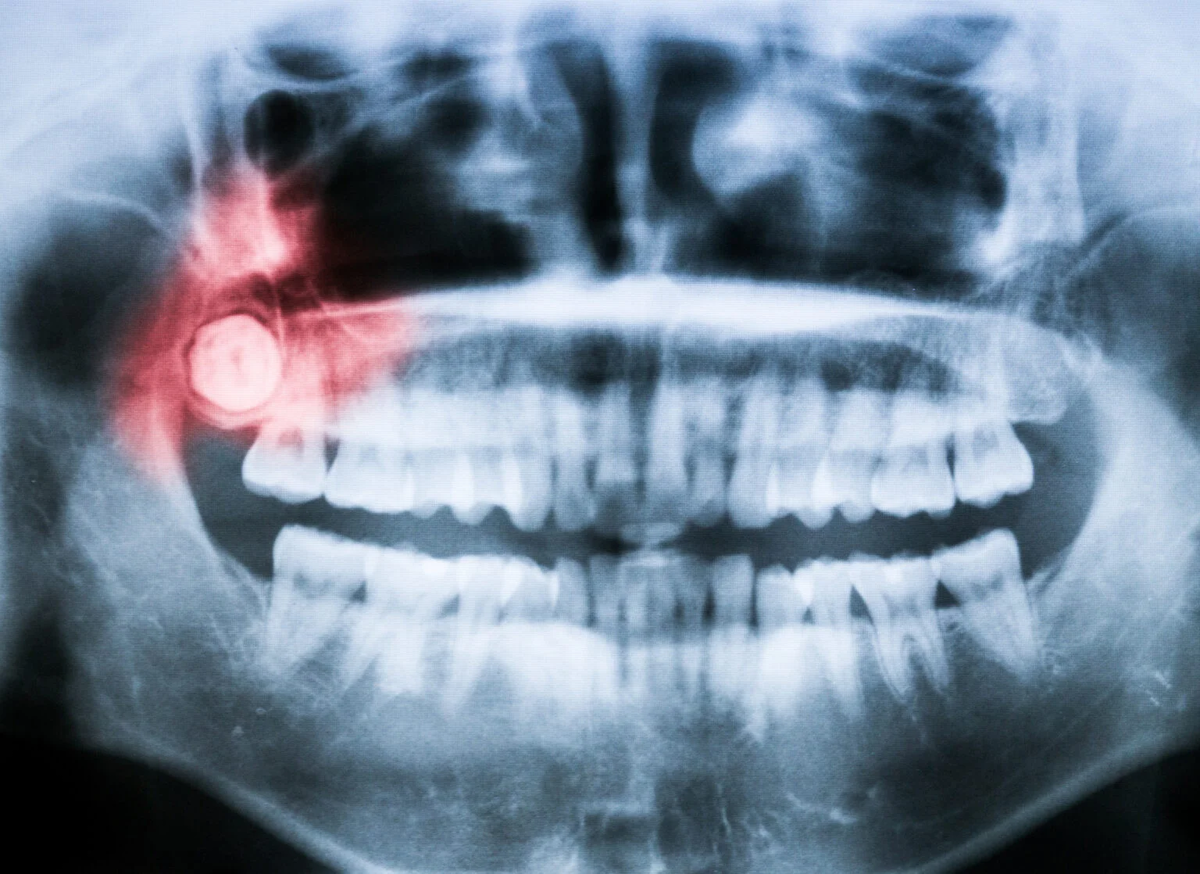

Темп нашей жизни тесно переплетается со многими вещами, такими как: гормональными изменениями и (конечно же) развитием зубов. Большинство из нас не помнит, как прорезались зубы, но многие помнят, как прорезались зубы мудрости, и, если вы живете в месте, где их регулярно удаляют, как их выдергивали из челюсти. Это всего лишь один из этапов развития зубов и один из трех этапов развития моляров, но до недавнего времени мы не знали, почему зубы мудрости появляются так поздно.

"Оказалось, что наши челюсти растут очень медленно, что, вероятно, связано с нашей общей медленной историей жизни и, в сочетании с коротким лицом, задерживает момент, когда механически безопасное пространство - или "сладкая точка", если хотите - становится доступным, что приводит к нашему очень позднему возрасту появления моляров", - объясняет Гэри Шварц, палеоантрополог из Института происхождения человека при Университете штата Аризона, соавтор статьи, в пресс-релизе. Легко забыть, что наши зубы, как и вся челюстная структура, испытывают значительное механическое давление при пережевывании пищи. А это значит, что челюсть должна быть готова к развитию зубов, расположенных в задней части рта, ближе к суставу. Если бы зубы мудрости появились раньше, моляры могли бы повредить челюсть, из которой они растут.

Все это является результатом двух фундаментальных особенностей человека: у нас длинная жизнь и короткие лица. Жизнь человека, какой бы короткой она ни казалась, довольно растянута по сравнению с другими существами, даже с другими приматами. Мы развиваемся медленно - мы не торопимся - и тратим чрезвычайно много времени на то, чтобы стать взрослыми. И, в отличие от наших кузенов-приматов, наши лица довольно плоские и приплюснутые. Просто взгляните на шимпанзе или горилл; вы заметите, что их челюсти выступают наружу, так что рот находится в основном перед мозгом (хотя вы, вероятно, никогда не думали об этом). Наши лица втянуты внутрь, располагаясь под мозговой оболочкой.

Сочетание этих факторов означает, что наши челюсти не могут вместить последний набор моляров до довольно позднего возраста.